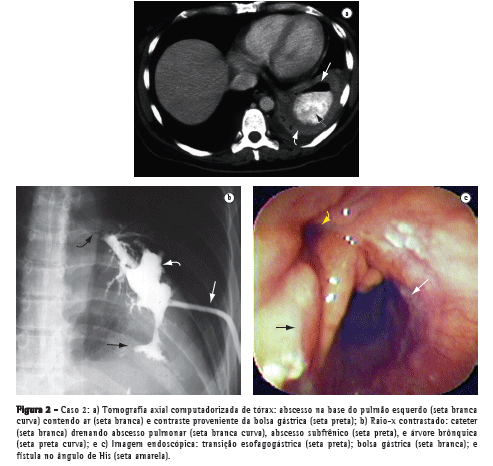

Um paciente do sexo masculino com 44 anos de idade submeteu-se à cirurgia de Fobi-Capella por videolaparoscopia para controle da obesidade mórbida, sendo reoperado após 48 h para tratamento de obstrução intestinal. Dois meses depois, foram realizadas duas sessões de dilatação endoscópica com balão para correção de estenose da anastomose gastrojejunal. Em seguida, o paciente apresentou quadro de vômica, tosse produtiva, febre e dor à inspiração profunda na região tóraco-abdominal esquerda, sendo diagnosticada uma imagem nodular de 7 cm de diâmetro, em base pulmonar esquerda, por meio de tomografia axial computadorizada de tórax (Figura 1a). O paciente apresentou melhora clínica após antibioticoterapia, fisioterapia respiratória e acompanhamento no serviço de pneumologia. Porém, houve duas recidivas num intervalo de três meses, quando então foi diagnosticada uma fístula gastrobrônquica por meio de imagem radiológica (Figura 1b) e endoscópica (Figura 1c) que evidenciou um orifício com 10 mm de diâmetro no ângulo de His, através do qual foi possível a passagem do endoscópio até uma pequena cavidade subfrênica onde se visualizava um orifício interno do trajeto fistuloso para a árvore brônquica. Não houve sucesso na tentativa de correção via laparotomia, sendo realizada apenas uma gastrostomia no estômago excluso para nutrição. Assim, usando bisturi elétrico, realizou-se a secção endoscópica da estenose gástrica e do septo situado entre a fístula e a bolsa gástrica associada à dilatação com balão de 20 e 30 mm (Boston Microvasive, Boston, MA, EUA) e aplicação de clipes na fístula (Olympus Corp., Tokyo, Japão). Após seis meses, observou-se aumento do diâmetro da bolsa gástrica, desaparecimento do referido septo e fechamento definitivo da fístula com resolução do abscesso pulmonar.